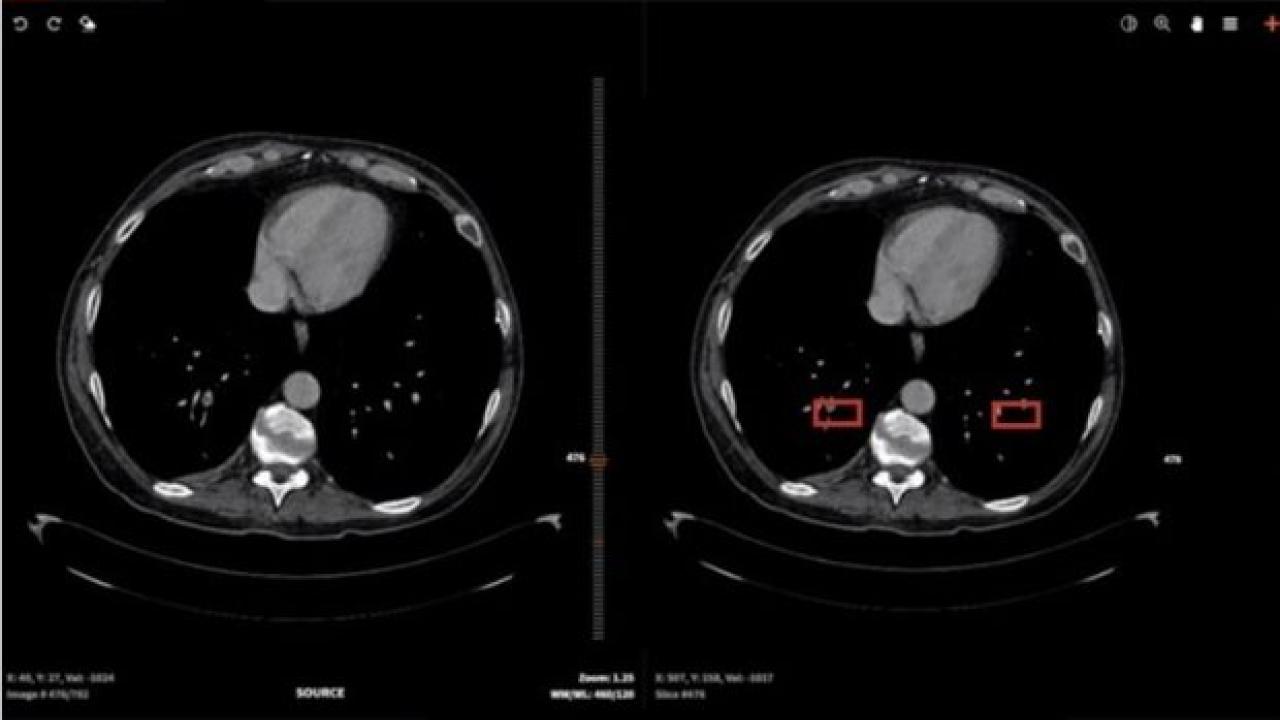

رئیس پژوهشکده فضای مجازی دانشگاه شهید بهشتی خاطرنشان کرد: پیش‌بینی و تشخیص با تصاویر CT قفسه سینه از قابلیت پیشگویی و حساسیت بالایی در تشخیص کرونا برخوردارند. بنابراین برای تشخیص زودهنگام کرونا بسیار مناسب هستند. هرچند درروش سنتی، تشخیص با بررسی حجم بالایی از اطلاعات تصویری توسط عامل انسانی انجام می‌گیرد که ازنظر سرعت و یکنواختی تشخیص بهینه نیست.

وی ادامه داد: همچنین برخی دیگر از بیماری‌های تنفسی علائمی مشابه با کرونا در این تصاویر دارند که باعث می‌شود عامل انسانی نتواند دقت زیادی در تفکیک بیماری کرونا از بیماری‌های مذکور داشته باشد. الگوریتم‌های هوش مصنوعی قادرند ضمن افزایش سرعت و یکنواختی تشخیص، دقت تفکیک کرونا از سایر بیماری‌های تنفسی را افزایش دهند.

طالب پور ادامه داد: به همین منظور بیش از ۱۰۰۰ تصویر CT از بیمارستان سینا دریافت و جدیدترین روش‌های هوش مصنوعی روی آن‌ها اعمال شد. به‌زودی با مقایسه نتایج روش‌های مختلف هوشمند، بهترین راهکار برای استفاده در پیش‌بینی و تشخیص زودهنگام کرونا در اختیار متخصصان قرار خواهد گرفت.